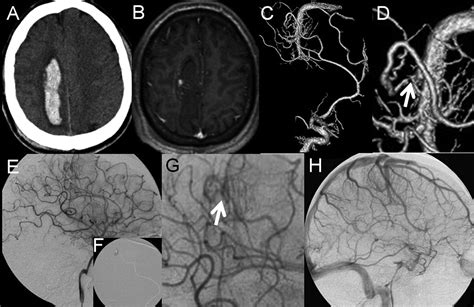

Learn about a Developmental Venous Anomaly (DVA), a common congenital brain vascular malformation. Discover why these benign venous variations are typically asymptomatic, how they appear on MRI or CT scans, and when neurosurgeons consider them clinically significant. Understand the risks and characteristics of this incidental vascular finding to better navigate your neurological health and diagnostic imaging results.